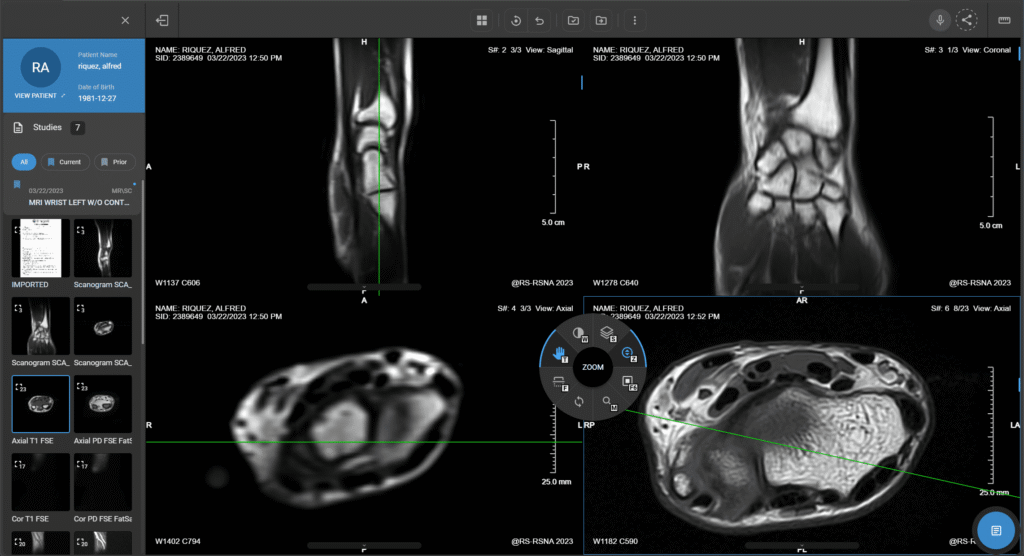

PACS en la nube y trazabilidad

Almacenamiento seguro y acceso a resultados en línea para seguimiento longitudinal y continuidad clínica con el médico tratante.